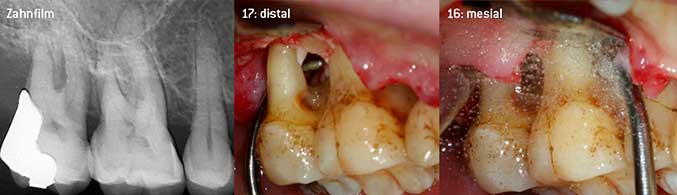

Als Initiatoren zur Entwicklung der neuen diamantierten Luftscaler-Spitze 3AP sahen es beide Zahnärzte als notwendig an, die Einschränkung in der Handhabung bisher kommerziell vermarkteter diamantierter Spitzen insbesondere während der Furkationstherapie oder in engen Knochentaschen zu verbessern. Dies sollte unabhängig von nicht-chirurgischem (Abbildung 2) oder chirurgischem Vorgehen sein (Abbildung 3).

Geschlossenes Debridement der Furkationen an 26 und 36

Abb. 2: Geschlossenes Debridement der Furkationen an 26 und 36 bei fortgeschrittenem Attachmentverlust

(Fotos Abb 2 -4: © Dr. Chr. Graetz)

Das Ziel bestand darin, eine universell einsetzbare Spitze zu entwickeln, um zeitraubende Spitzenwechsel zu vermeiden. Daneben sollte aber die Anwendung der neuen Arbeitsspitzen sowohl in engen Knochentaschen von distal als auch am distalen Furkationseingang von Oberkiefermolaren einfacher sein und infolgedessen eine effektivere Instrumentierung ermöglichen. Dies wurde durch einen größeren Durchmesser des Instrumentenbogens (Abbildung 1) erreicht, was gerade bei Zähnen mit fortgeschrittenem Attachmentverlust und Furkationsbeteiligung von großem Vorteil während des geschlossenen Debridements ist (Abbildung 4).

Geschlossenes Debridement der Furkation an 16

Abb. 4: Geschlossenes Debridement der Furkation an 16 bei fortgeschrittenem Attachmentverlust